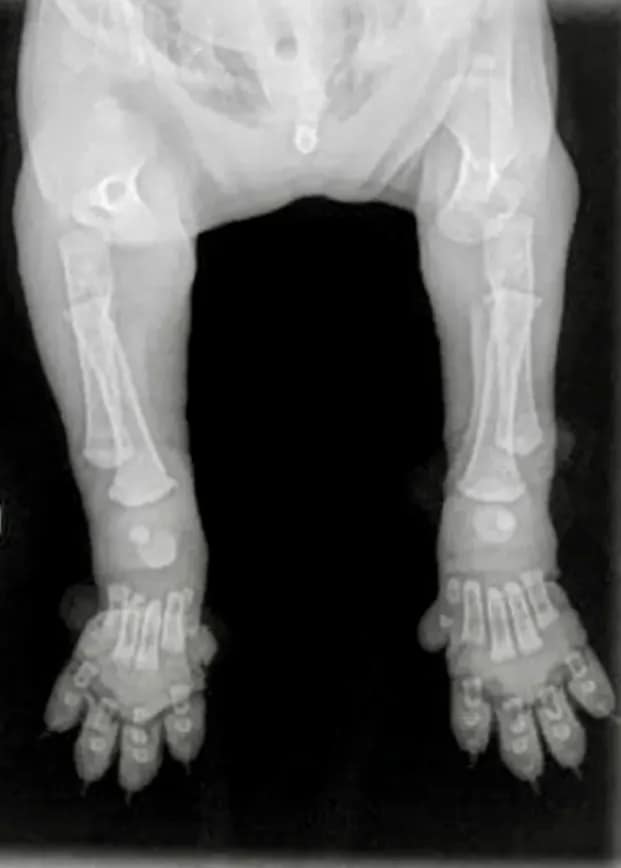

Growth plates (also called epiphyseal plates) are soft areas of cartilage located at the ends of long bones. As your puppy matures, these plates slowly harden (calcify) and turn into solid bone.

For healthy development, bones must grow evenly and at the same rate. This synchronized growth is critical for producing correct structure, balance, and movement — especially in powerful, muscular Bully breeds.

Until the growth plates fully close, they remain vulnerable to injury. They are actually the last part of the bone to harden.

One of the most common areas for growth plate issues is between the radius and ulna in the front leg. If one bone stops growing and the other continues, it can result in bowed legs and an abnormal gait that affects the dog permanently. Over time, this imbalance can place stress on other joints and lead to secondary issues such as arthritis or ligament strain.

X-Ray of a puppy